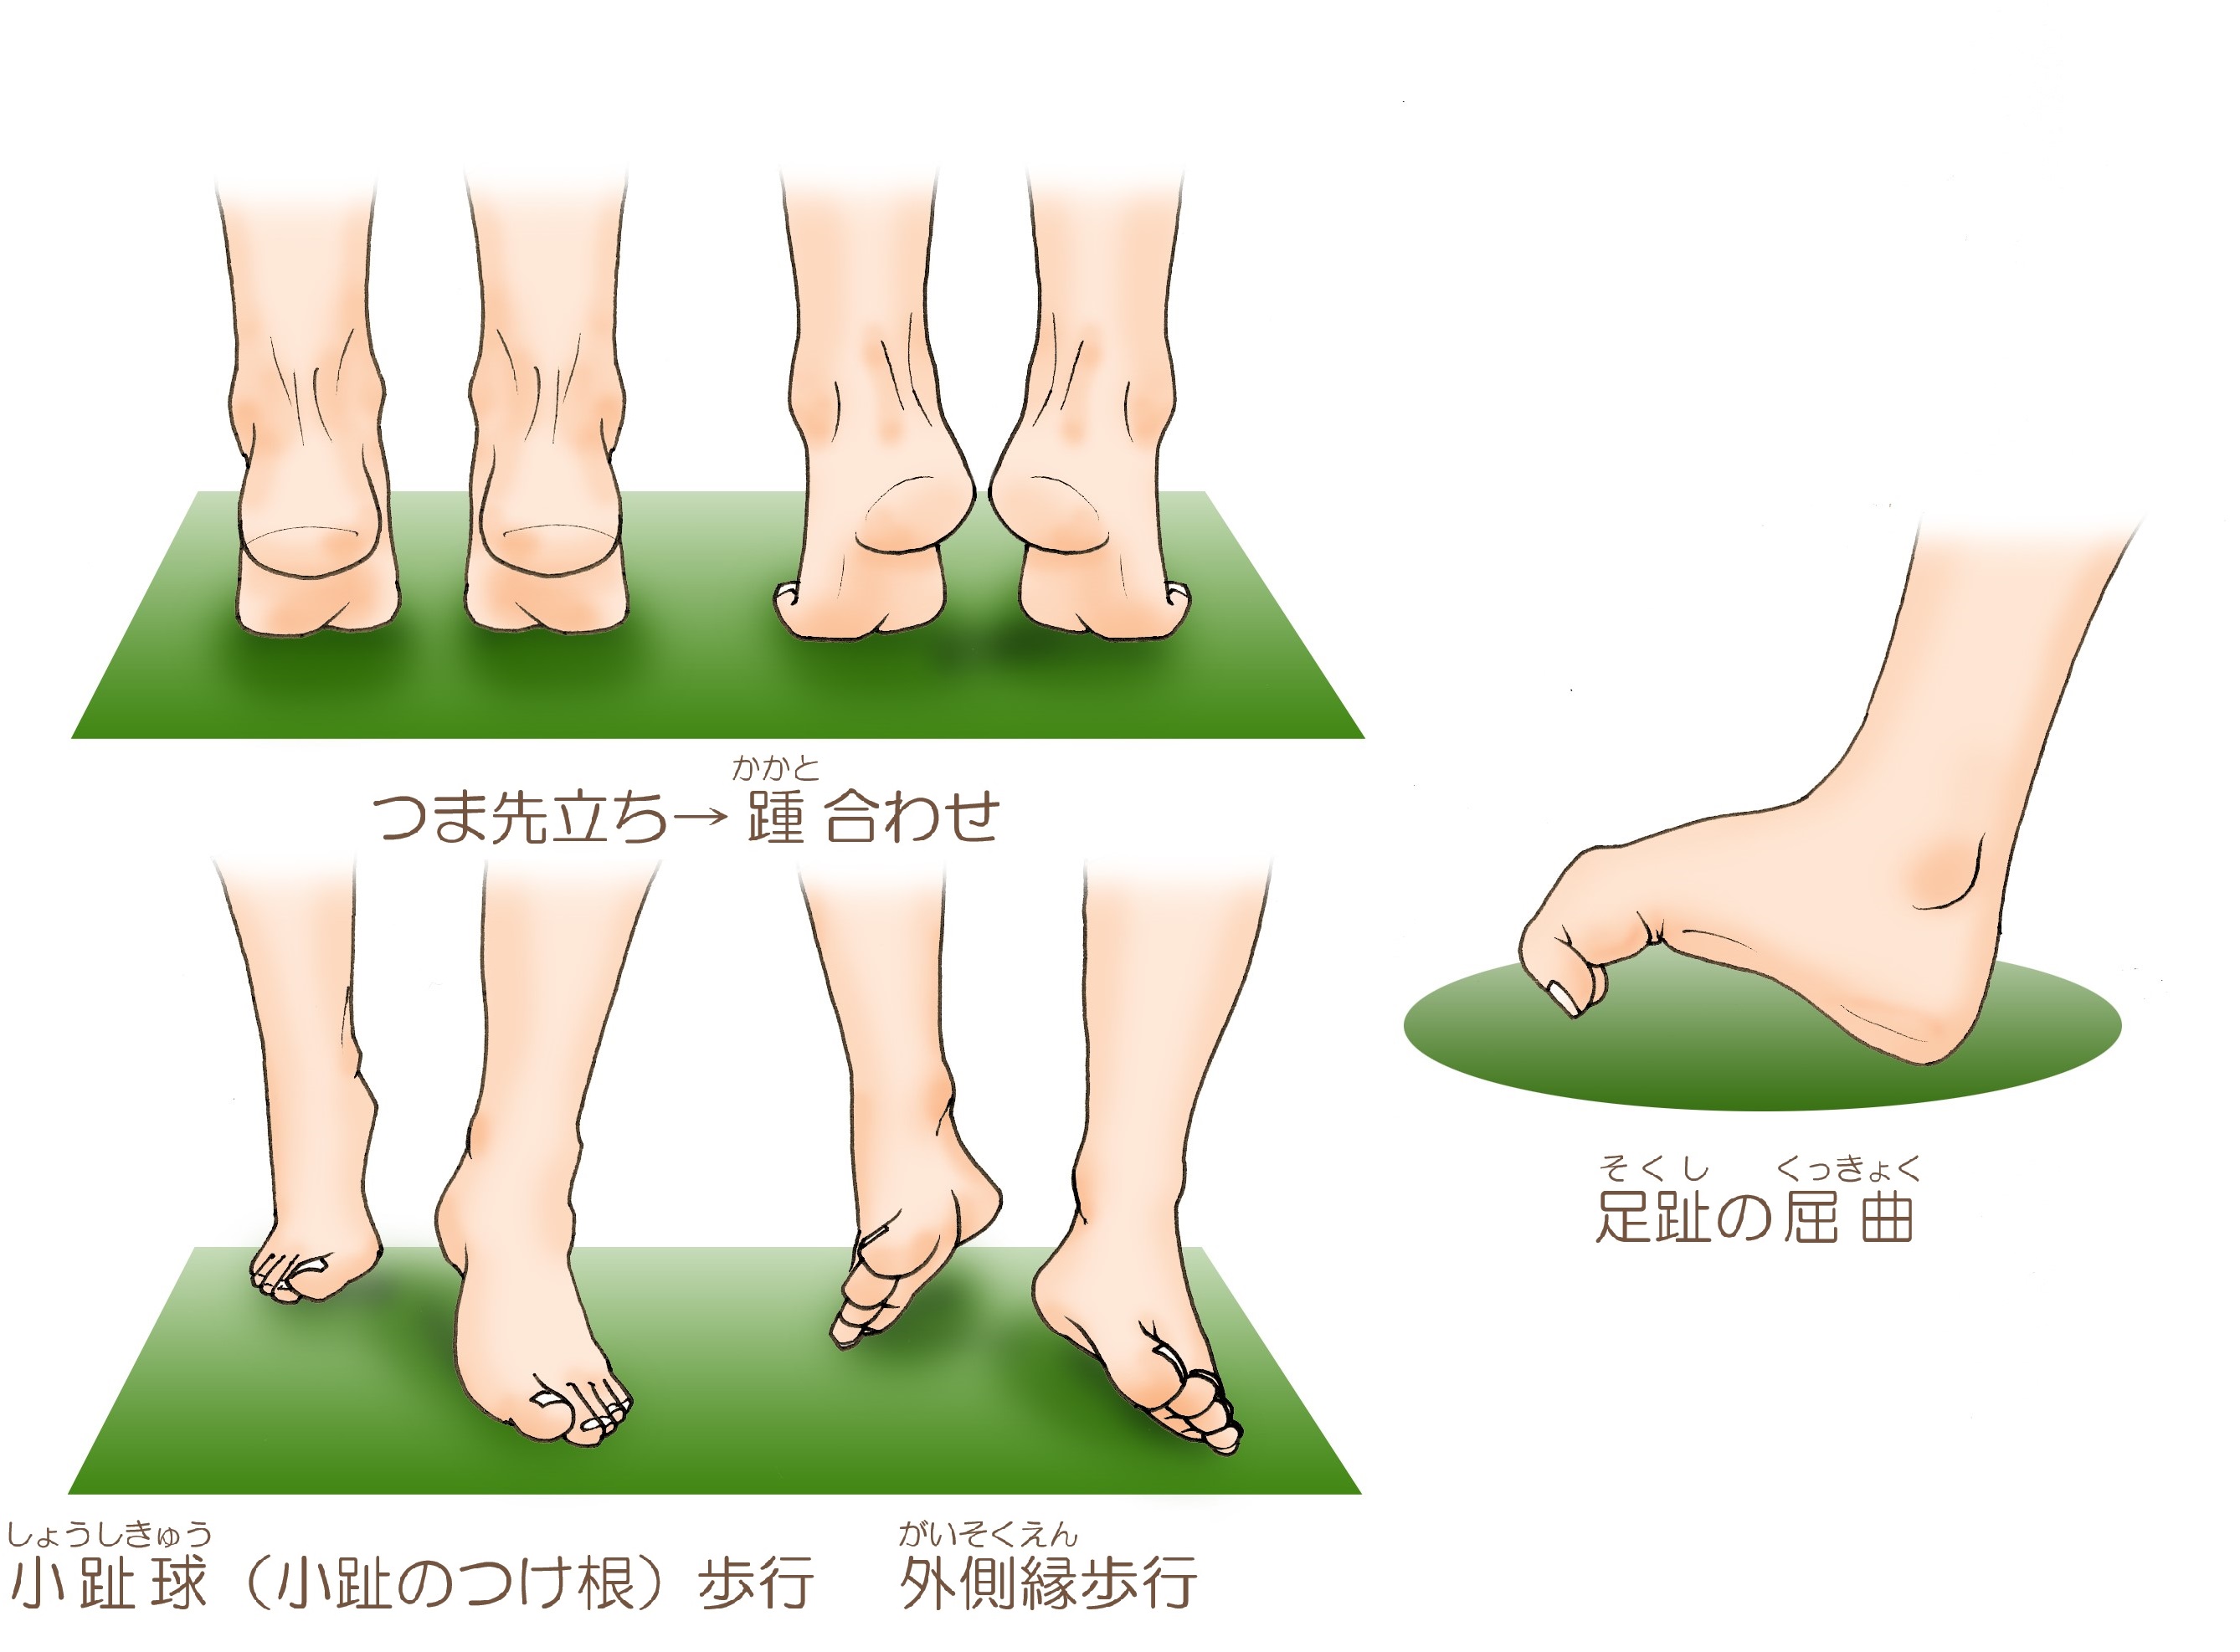

湿布の効果は何時間?短い時間でも効果はある?薬剤師が湿布 捻挫した場合にサポーターはいつまで着ける?その期間とは!? 足関節(足首)捻挫には湿布?アイシング?テーピング?捻挫 捻挫を早く治したいときは?捻挫の対処方法と処置の捻挫によくある症状 温感湿布と冷間湿布のどちらを使えばいいのか分からない 応急処置はどう対処したらいいのか知りたい 捻挫がクセになってしまいそうで不安 捻挫を未然に予防する方法を知っておその前に、説明を分かりやすく するために、 足首捻挫の分類から説明します。 足首を捻った(ひねった)方向による分類 一般的には大きく分けて、2つのタイプの捻挫があります。 一般的な捻挫の分類 1.内返し捻挫(内反強制) 足を内側に捻る 2.

子供 捻挫 足首 湿布-足首 捻挫 湿布 捻挫で湿布を使用する期間はいつまで?冷やす 足首捻挫の湿布の貼り方や位置は?貼る期間は?寝るときは 捻挫でモーラステープの使用方法!湿布としての効果は高い! 捻挫(ねんざ)の対策|くすりと健康の情報局;足首の捻挫、くせになっていませんか?歩くとすぐ足首が痛くなりませんか? 捻挫や靱帯損傷のあとなど足首が不安定になり起こる症状を軽減するリハビリの方法です。 ⓪準備 運動する側の足のかかとがベッドの外に出るように伸ばします。